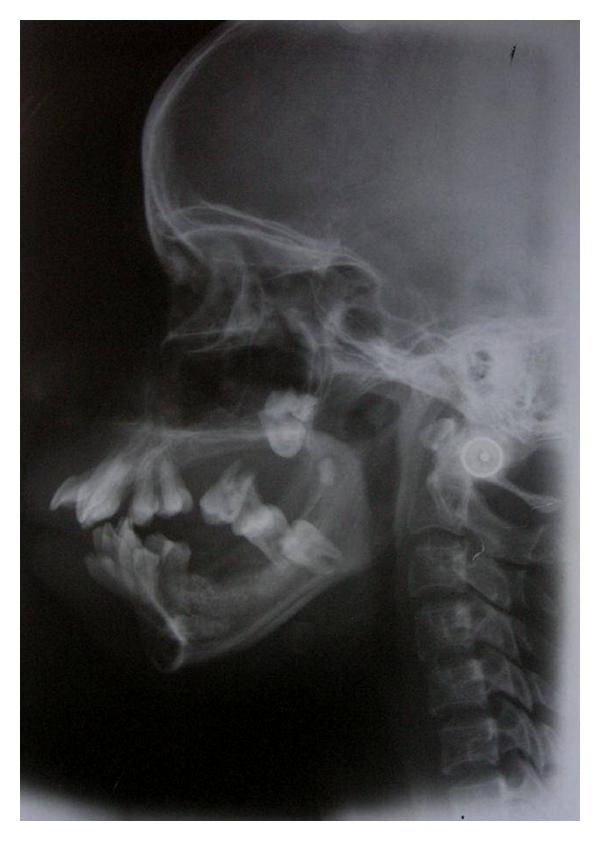

SCP-7202增生未受治疗后造成的牙齿错位。

描述: SCP-7202是一种异常性的牙科病症,特征为牙龈发生快速的过度生长。SCP-7202产生的过剩牙龈组织一般多孔、敏感且易于出血。由于发展速度极快,若无手术干预,牙龈组织可能会在数周之内将牙齿闭塞、妨害下颌活动。

SCP-7202会影响到身处基金会Site-5331D周边范围内任何具有牙龈组织的活体生物。SCP-7202的发展速度与在范围内的停留时长大致成正比。